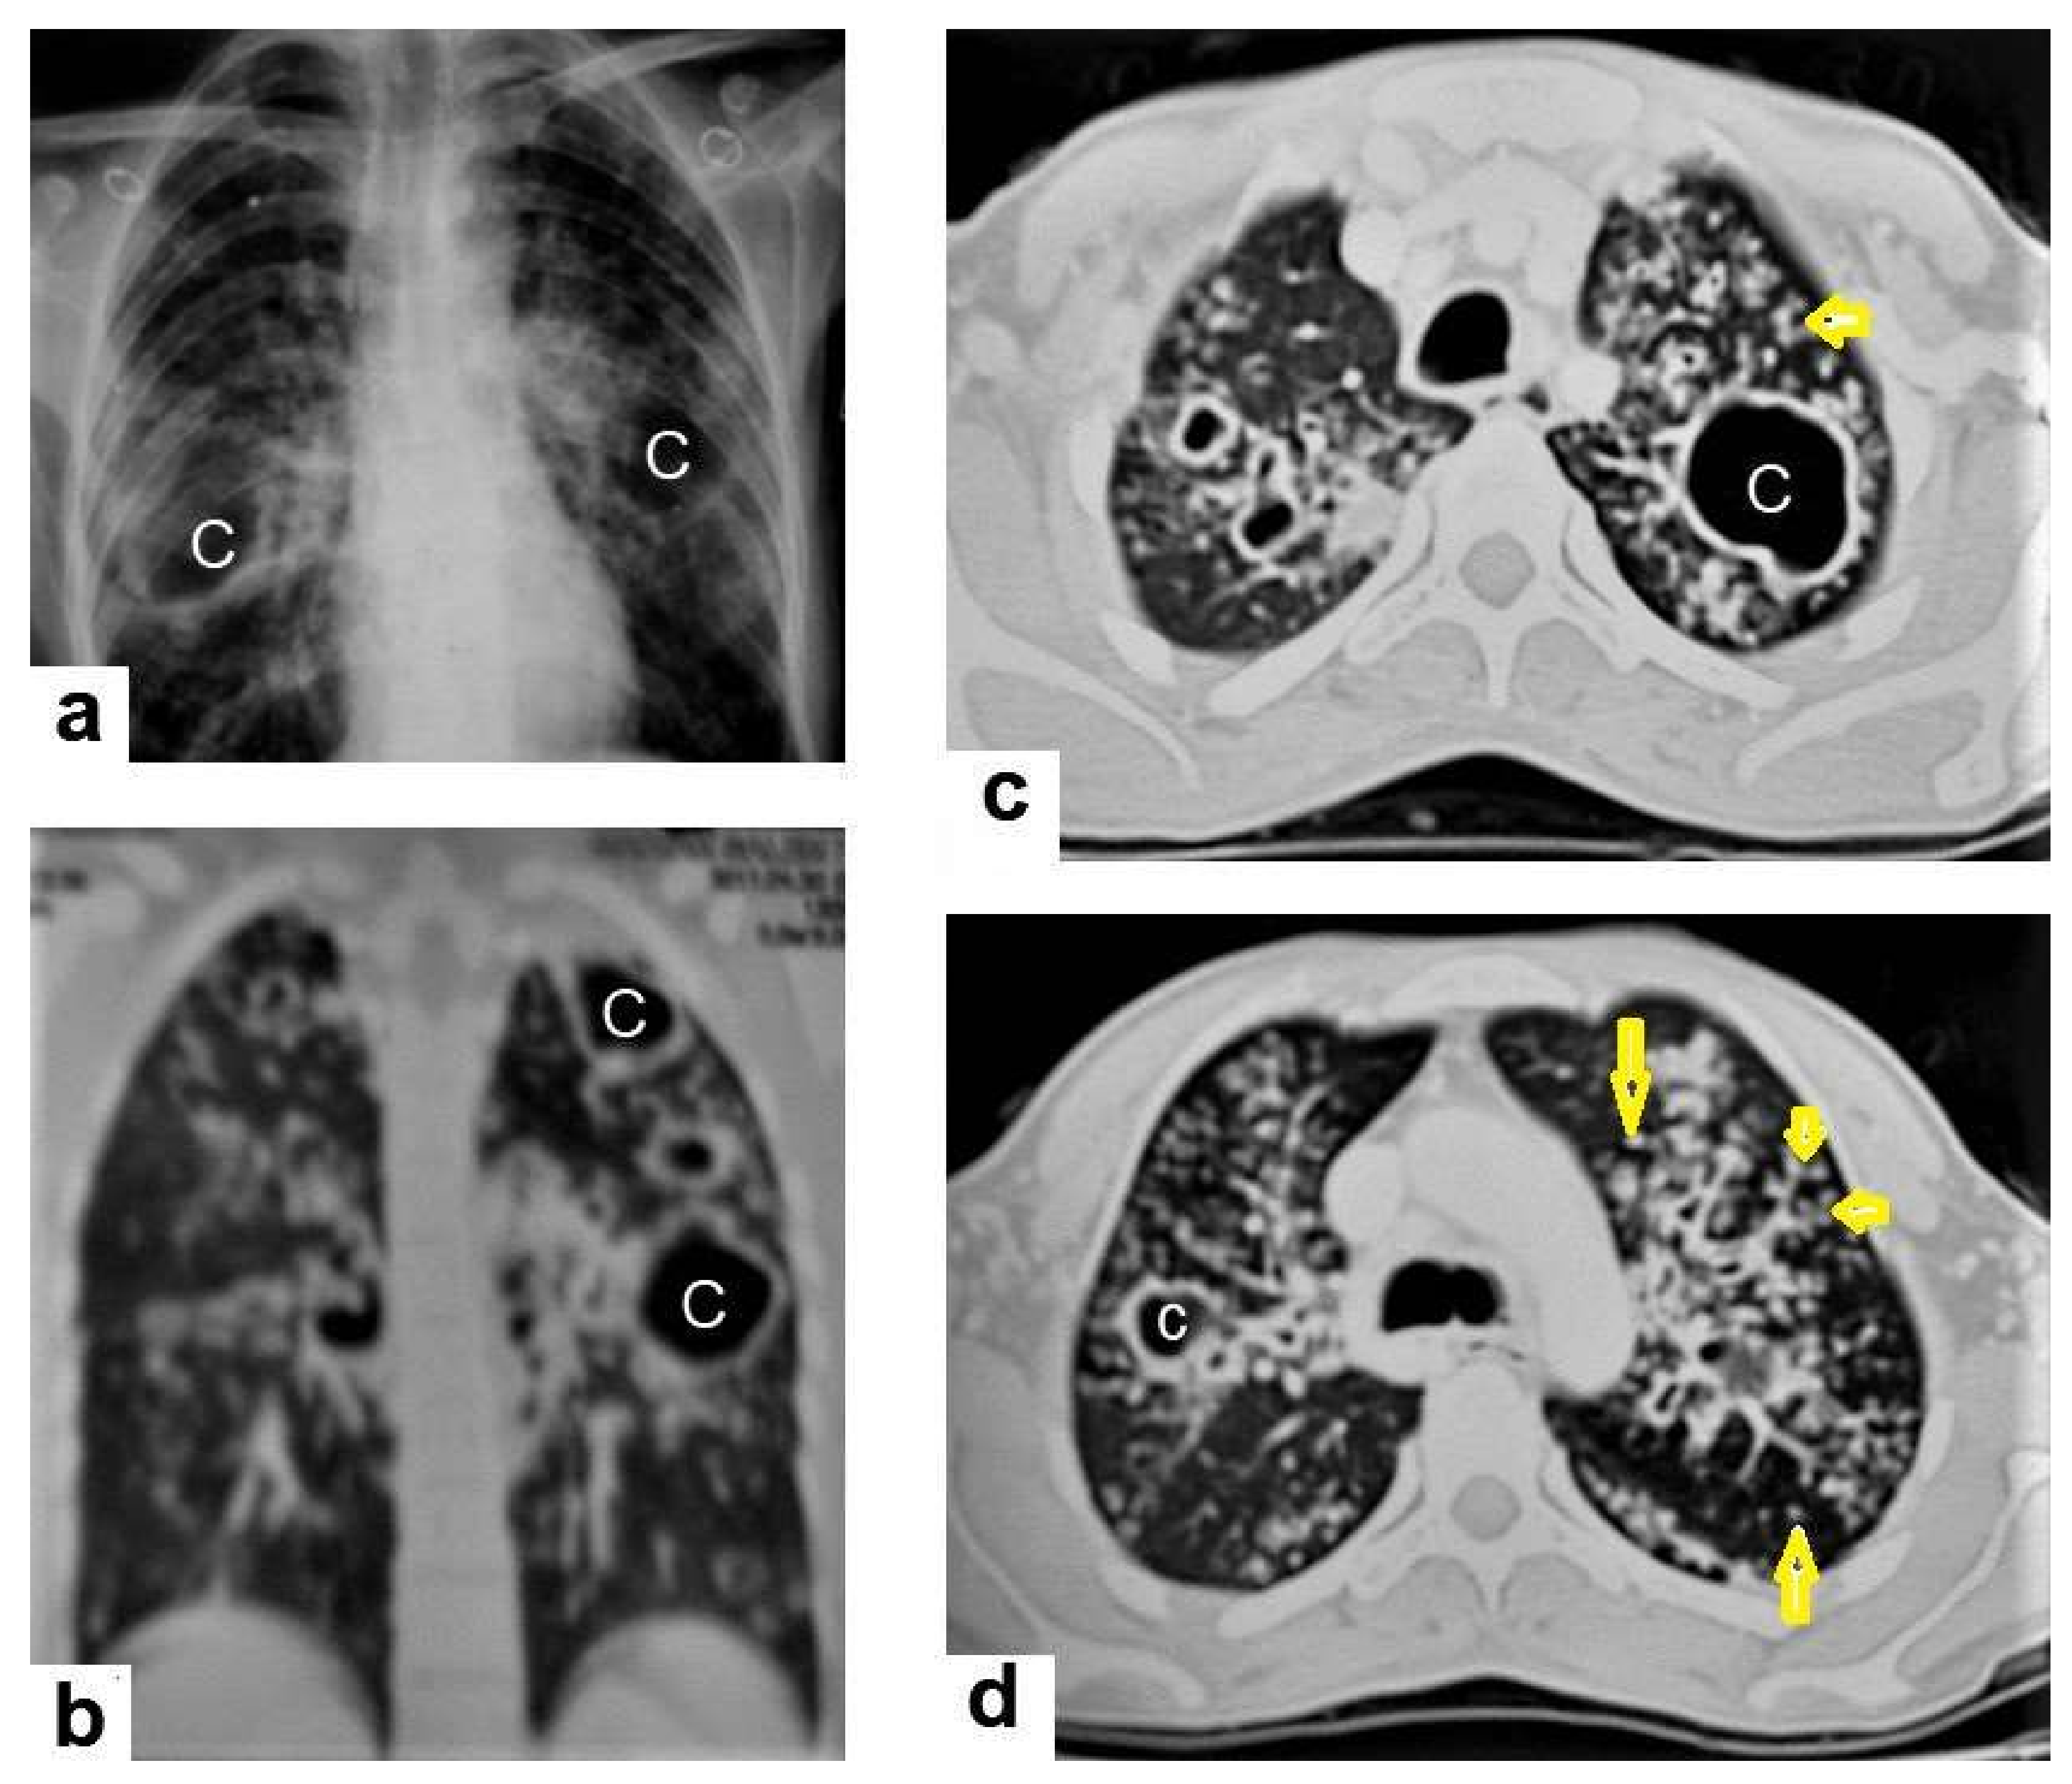

• Miliary TB (Figure 6 and Figure 7) appears as innumerable small (1–3 mm) granulomas with random distribution in the lungs and other organs with a predominance to the lung bases due to the gravity-dependent high blood flow. It occurs due to the hematogenous dissemination of mycobacterium tuberculosis bacilli, especially in immunocompromised patients and children [1,13]. Miliary TB is a significant differential diagnosis of pulmonary metastasis from thyroid cancer or others, even in children [19].

Figure 4. Reactivated TB in a 34-year-old women. (a) Chest radiograph shows extensive reticular shadowing and multiple cavitary lesions in both lungs. (b) Coronal reconstruction CT shows multiple cavitary lesions (c) in both lungs, the large two in the posterior segment of the upper lobe, and in the apical segment of the lower lobe of the left lung. (c,d) Axial CT images of the lung show multiple cavitary lesion, the largest in the posterior segment of the left upper lobe, with multiple centrilobular (long arrows) and tree-in-bud (short arrows) appearance.